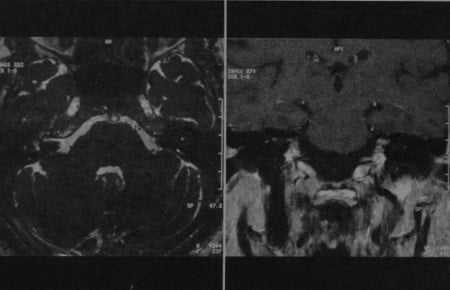

(Слева) На рисунке в аксиальной плоскости показана крупная шваннома лицевого нерва (ШЛН), состоящая из компонентов ММУ («мороженое») и ВСК («рожок»), напоминающая вестибулярную шванному. Поражение лабиринтного сегмента лицевого нерва позволяет сделать заключение.

(Справа) При аксиальной MPT T1 ВИ С+ FS у пациента с односторонней ней-росенсорной тугоухостью визуализируется ШЛН с компонентами ММУ и ВСК. Обратите внимание на «хвост» лабиринтного сегмента лицевого нерва, позволяющий отличить ШЛН от вестибулярной шванномы.